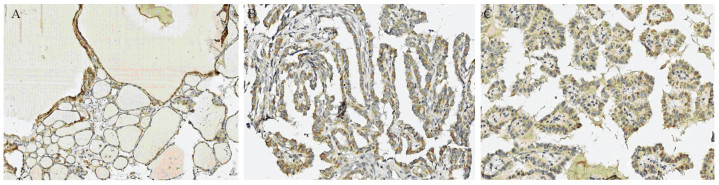

Methods Paraffin blocks from 90 cases of thyroid lesion were collected to make tissue microarray. The expression of S100A14 and LOXL2 in 30 cases of nodular goiter (NG), 30 cases of classic papillary thyroid carcinoma (CPTC) and 30 cases of high invasion papillary thyroid carcinoma were detected by immunohistochemistry. The correlation of S100A14 and LOXL2 expression with the clinicopathological characteristics of papillary thyroid carcinoma patients was investigated.

Results S100A4 and LOXL2 were highly expressed in papillary thyroid carcinoma. There was a gradually increasing trend from the expression in NG group, CPTC group to high invasive group. The positive rate of S100A14 in papillary thyroid carcinoma with lymph node metastasis was higher than that without lymph node metastasis (P < 0.05). There was significant difference of S100A14 and LOXL2 expression between CPTC group and high invasion group (P < 0.05). S100A14 expression was positively correlated with LOXL2 expression (r=0.332).